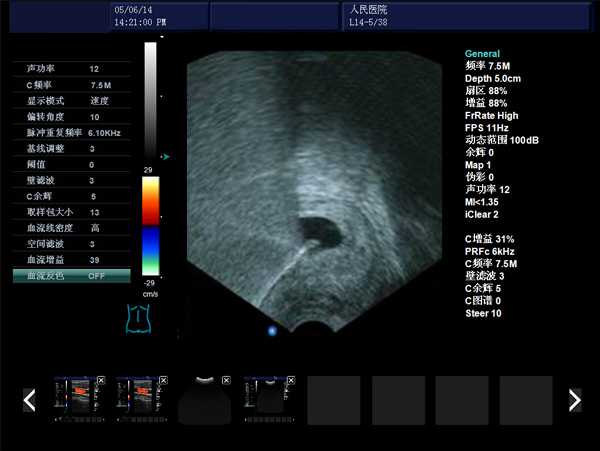

DW-480全數字超聲婦產科手術監視儀

產品性能

高集成數字式

寬頻探頭,頻率范圍從2.0MHz到10.0MHz

強勁的組合式模塊化軟件設計

全數字式大容量圖像存貯和文件歸檔管理

操作系統簡單靈活

探頭與陰道窺器相結合,不進入宮腔,不占手術宮頸空間,手術更方便

實時動態高線密度超大角度掃描,有效提升橫向分辨力和側向分辨力、圖像自然更清晰

采用大容量電影回放,實時精微顯示等全數字圖像處理技術,宮腔內部圖像清晰可辨,不容錯過一點殘留,手術干凈徹底,避免了吸宮不全、漏吸等并發癥的發生